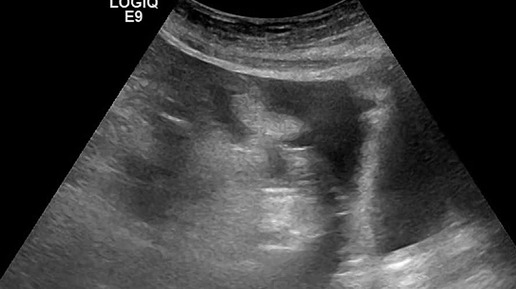

Видео к статье: "Свободная жидкость в брюшной полости"https://dzen.ru/a/Z-1KdOK-KyrjRiGF

Ультразвуковые находки от врача УЗД Зорина Я.П.